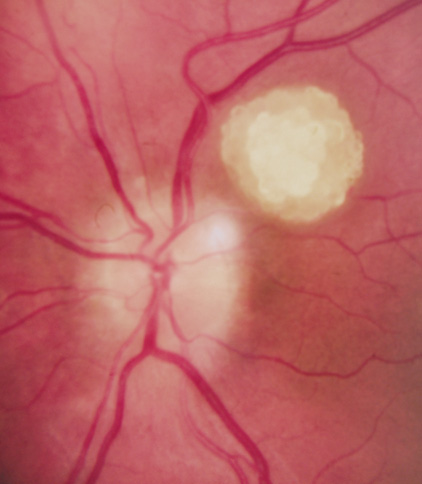

Astrocytic Retinal Hamartomas

Although in Van der Hoeve's original description the term phakoma or phakomata was a generic term for the tumors occurring in various organ systems,1 it has become associated with the retinal astrocytic tumors of TSC,3 which occur in about 50% of affected patients and are bilateral in 25% to 30% (Table 3, Fig. 16).154,156

Fig. 16. Tuberous Sclerosis Complex: astrocytic retinal hamartoma, also referred to as retinal phakoma. There are three types: translucent type (a), calcified, nodular or “mulberry” type (b), and intermediate type (c).156 These usually do not affect vision and require no treatment. About half of patients are affected and there are bilateral lesions in 25% to 30%.154–156

Type 1. In the most common type, relatively flat, smooth-surfaced, and translucent lesions often difficult to see (an abnormal light reflex may be the only clue). They are in the posterior pole, superficial to the retinal vessels.156

Type 2. Raised, calcified, multinodular (“mulberry-like”) tumors in the posterior pole (80% within 2 disk diameters of the optic nerve).156

Type 3. The least common, intermediate type shows features of types 1 and 2, often in the posterior pole.156

Historically, the presence of mixed (type 3) hamartomas led to the suggestion of evolution from the type 1 to the type 2.157 A long-term photographic study found that although the types remained unchanged, a minority of types 1 and 3 increased in calcification and a new lesion was noted that had not been evident on an earlier photograph.157 All three types of retinal hamartomas may be found in young children. There is no correlation between age and the predominant type of lesion.156

Histologically, phakomata are composed of glial astrocytes—elongated, fibrous astrocytes with small oval nuclei, arising from the retina or the optic disc. The type 2 lesions contain basophilic, calcified drusen-like deposits within a dense vascular network. On fluorescein angiography, the type 2 lesions show autofluorescence, leakage with transit of dye, and marked late hyperflorescence.3,113

Astrocytic retinal hamartomas usually do not affect vision and require no treatment. Vitreous seeding and vitreous hemorrhage have been reported in association with phakomata, but these are rare.158,159 Laser photocoagulation may be considered in rare cases were exudation induces serous retinal detachments.160 The differential diagnosis of “white retinal lesions” includes retinoblastoma, toxoplasmosis and toxocara.3,113